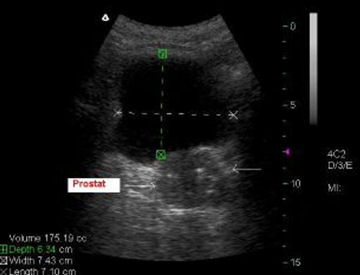

Üriner sistem sonografisi